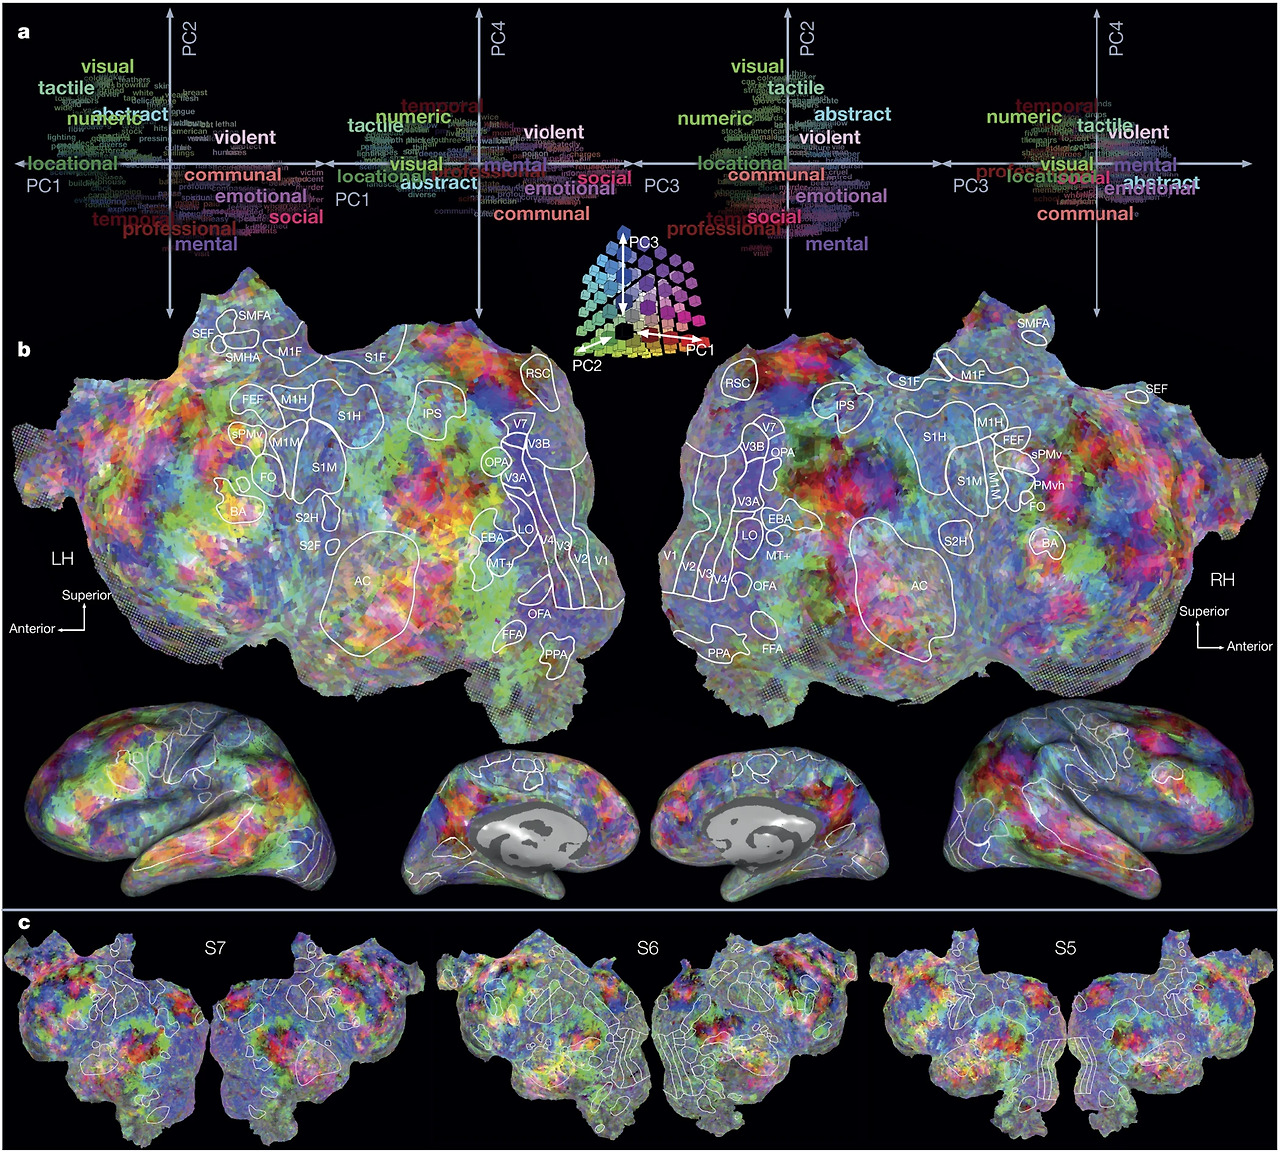

흥미로운 부분은 BOLD 이미징 기술의 개발 후 수많은 세계적인 뇌과학자들이 이를 이용하여 동물뿐 아니라 사람의 뇌의 이미징에 사용하게 되었다는 것입니다. 환자의 뇌의 활성화되는 부위를 관찰하므로 질병과 연결시킬 수도 있었습니다. MRI에 새로운 기능을 부가했다고 하여 fMRI (functional MRI, 기능성 fMRI)라고 부르고 있습니다. 최근에는 fMRI 통해 사람이 어떤 사물을 관찰하고 있는지 무슨 생각을 하고 있는지에 대한 패턴을 분석할 수 있게 되었습니다. 단적인 예로 영화를 시청하는 사람의 뇌를 분석한다고 합시다. 영상에서 나오는 사물과 내용에 따라 다른 fMRI 이미지가 생성되는데 특정 사물을 볼때 마다 그 이미지의 패턴이 반복적이고 일관되게 나타남을 알게 되었습니다. fMRI는 사람이 보고 있는 사물과 생각하는 것까지 간접적으로 파악할 수 있는 '사람의 마음을 읽는 기계'로 거듭나게 되었습니다. 근래는 컴퓨터 분석 특히 인공지능, 머신러닝을 통해 좀 더 명확하게 분석되고 있습니다.

fMRI pattern.jpg 신호의 패턴에 따라 단어를 설정하여 어떤 영상을 보고 있는지를 분석해낼 수 있다 (UC버클리 대학 Jack Gallant교수 연구)